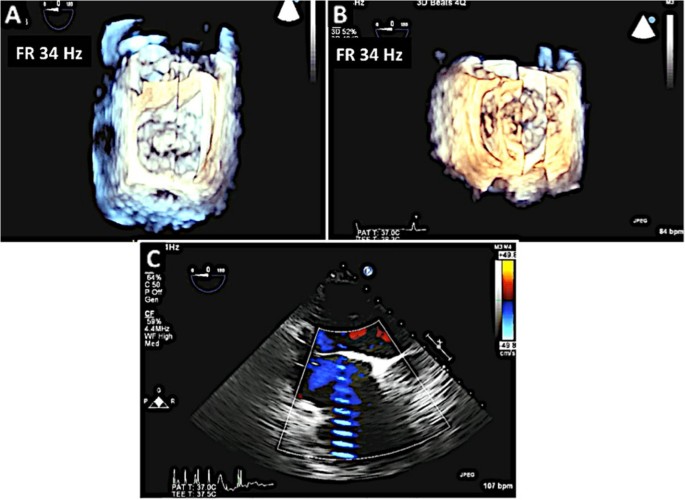

Multiplane 2D TEE with color Doppler is utilized to identify the mitral valve scallops. Panel A demonstrates a TEE at midesophageal 0 degrees view. In this view one can visualize the A2 and P2 scallops of the mitral valve at the tips of the leaflets. However the scallops visualized depend on the level of depth. At 0 degrees midesophageal view, when the aortic valve is visualized, the A1/P1 scallops are noted at the leaflet tips. When the TEE probe is advanced further into the esophagus past the midesophageal level, the A3/P3 scallops are identified at the leaflet tips [16]. Of note, the A2 scallop of the mitral valve is flail with a posteriorly directed mitral regurgitation jet. Panel B demonstrates a commissural view at 60 degrees. In this view, the lateral most scallop (close to the appendage) is P1. One can also visualize the central, flail A2 scallop. The P3 scallop is also well visualized in this view. The mitral regurgitation originated around the A2 scallops as was seen in the 0 degree view. Panel C is the long axis view between demonstrating the A2 and P2 scallops.

2D and color Doppler assessment of Type II MR. A: 2D TEE at 0 degrees demonstrates severe posteriorly directed MR due to a flail A2 scallop. B: TEE at the bicommisural view again demonstrates the origin of the MR. C: The origin of the MR is between the A2/P2 scallops. The coaptation-septum distance is also demonstrated.